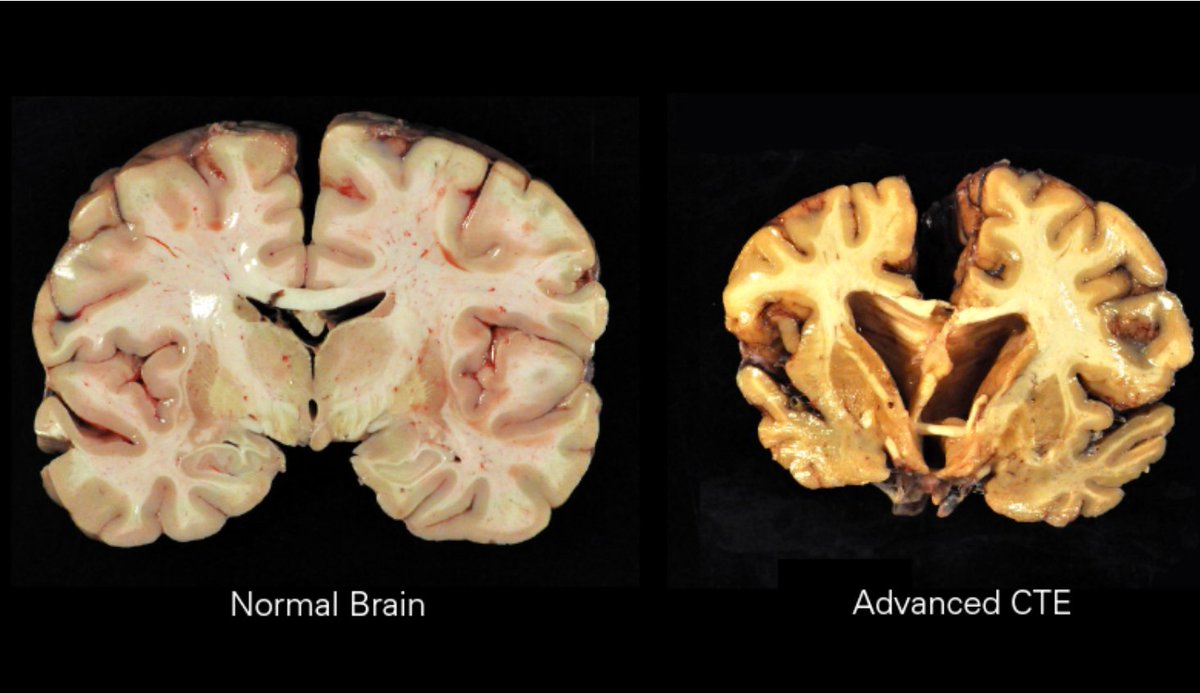

يمكن أن تؤدي ضربة الرأس إلى حالات مثل اعتلال الدماغ المزمن (CTE)، مما يؤثر على المزاج والسلوك والإدراك. يعد الاكتشاف المبكر والوقاية أمرًا أساسيًا، لأن الضرر كثيرا ما يكون غير قابل للعلاج.